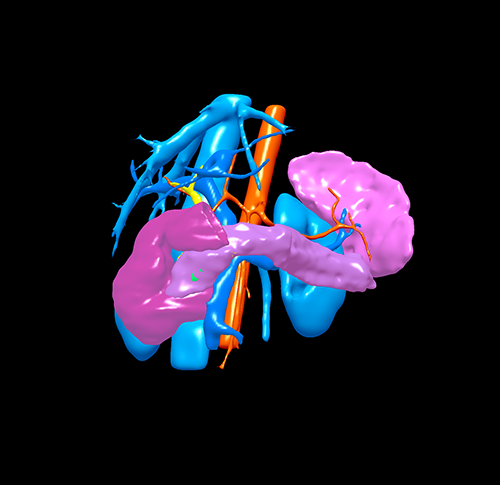

胰腺头颈假性乳头状瘤 -胰腺中段切除